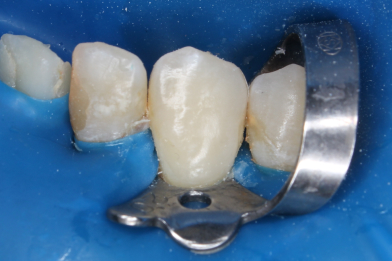

Для чего нужен КТ снимок? Не всегда можно увидеть кариес невооружённым взглядом. Данный

Бояринов Сергей Эдуардович

случай показывает наличие скрытого кариеса, который образовался на контактной поверхности

4.5 зуба. Именно наличие такого кариеса можно обнаружить при тщательной диагностике с

применением КТ снимка. -

Выполнена изоляция рабочего поля. Под инфильтрационной анестезией раствором Артикаина 1:100000 1,7 мл. Препарирование кариозной полости зуба. Пломба Ceram•X™ светового отверждения. Анатомическая форма зуба и целостность контактного пункта восстановлены

Бояринов Сергей Эдуардович -